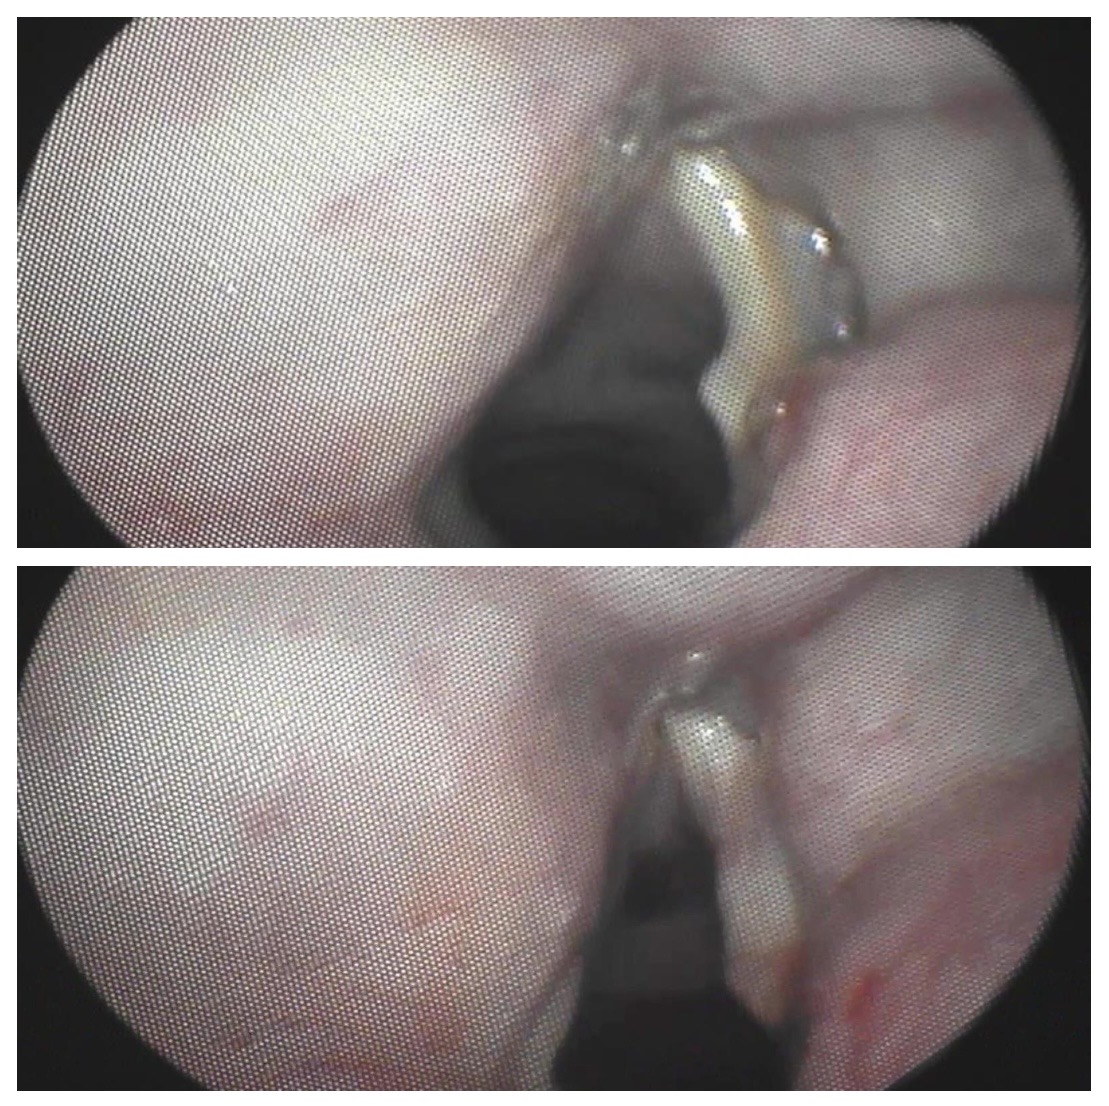

Ambas imágenes muestran antes y después de la medialización con ácido hialurónico del pliegue vocal derecho paralizado. Se observa la rectificación del mismo.

Durante la fonación inmediatamente luego de la inyección se observa el cierre glótico completo (objetivo deseado)